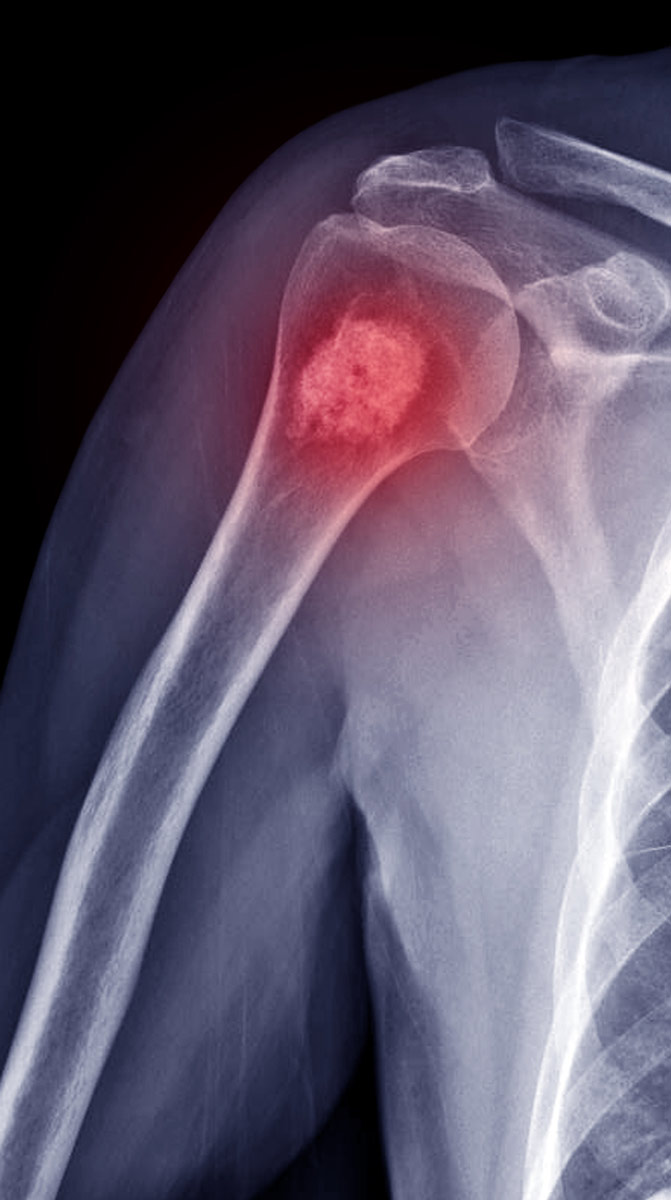

Tumorales

¿Qué son las enfermedades Tumorales?

Son enfermedades en las cuáles se produce un crecimiento exagerado o anormal de las células de nuestros tejidos.

Existen tumores “benignos”, en los que lo único que existe es una multiplicación anormal de las células, que puede poner en compromiso el organismo por compresión de estructuras vecinas. En los tumores “malignos”, lo que llamamos “cáncer”, las células dejan de parecerse a las normales, se dividen rápidamente, acaban destruyendo tejidos sanos y pueden migrar a otros órganos.